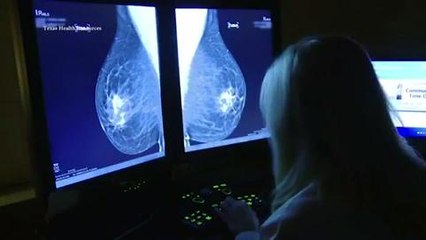

Huge drop in cancer screenings during COVID-19 pandemic

Figures from the Australian Institute of Health and Welfare show a 45 drop in the number of women getting screened for cervical cancer in the first half of this year.